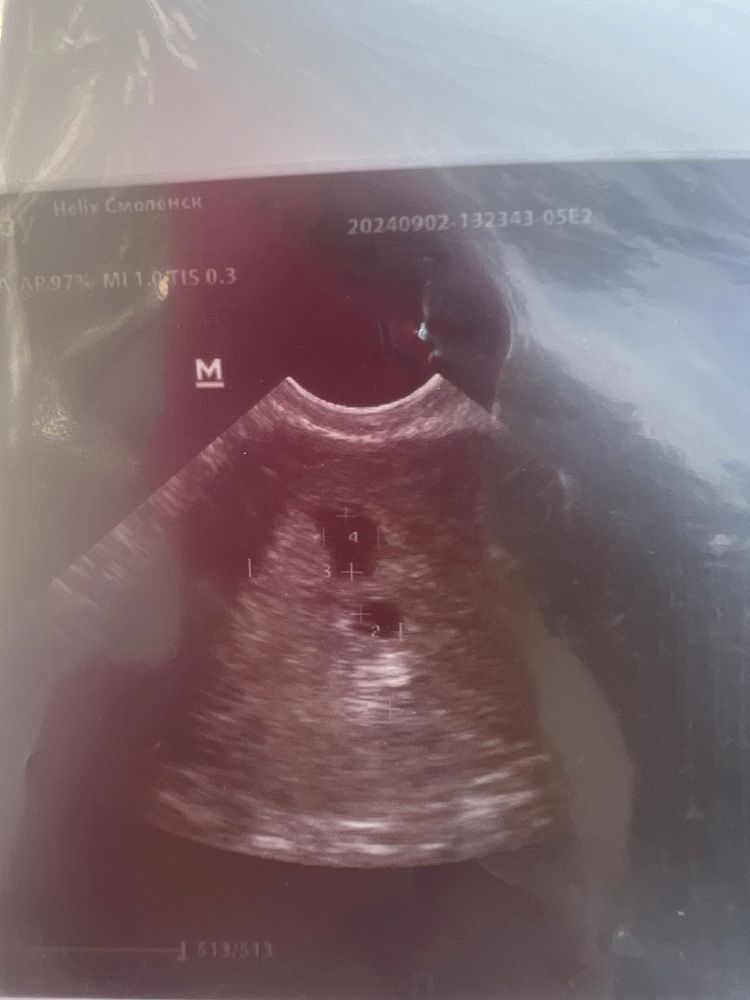

Добрый вечер, подскажите пожалуйста, акушерских 6,4 недели, на узи нашли плодное яйцо 4,6 мм, эмбриона нет. Появилась отслойка 6,8*6 мм.

Есть ли шанс сохранить?

Эмбрион обычно ждут до размеров ПЯ 25 мм. Но у вас оно не соответствует сроку. Возможно, действительно, поздняя овуляция была? Вы не отслеживали? Хгч не сдавали? Узист что сказал? Я бы дня через 3 переделала для контроля.

Маленькое ПЯ для вашего срока. Возможно, поздняя овуляция, повторите УЗИ через неделю.